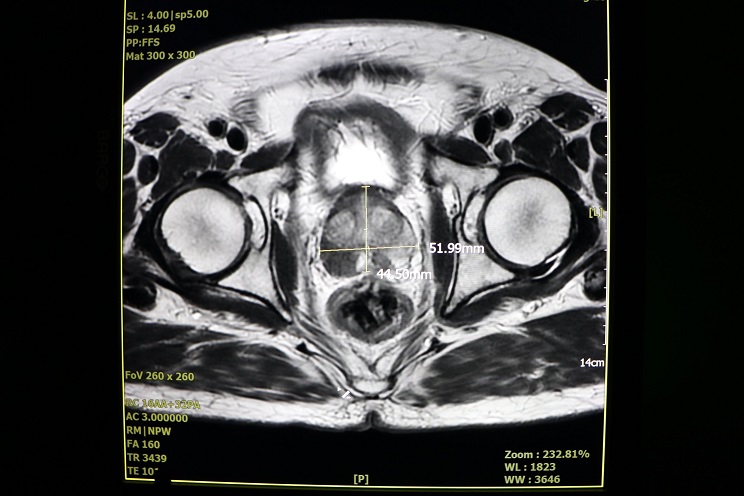

▲攝護腺腫大超音波檢查照。朱懿柏提醒,當男性出現「尿失禁」問題時,往往代表攝護腺肥大已進入晚期階段,膀胱功能出現損傷跡象。他說明,尿失禁主要可分為以下三種類型:

4.超音波:可以正確測量攝護腺大小與膀胱殘留尿量。